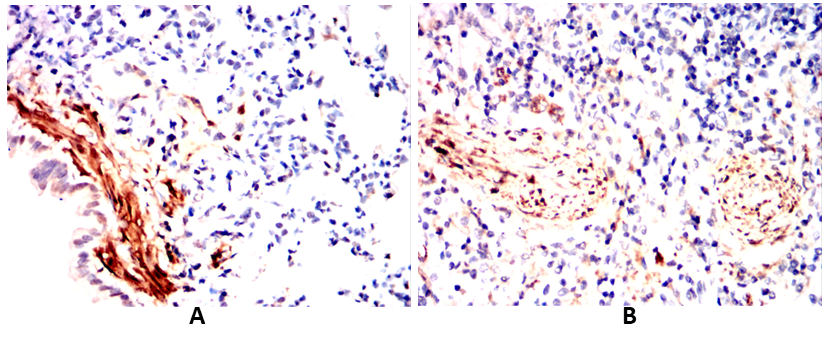

2. **《CNN1 Expression in Leiomyosarcoma: Diagnostic Utility of a Novel Monoclonal Antibody》**

作者:Chen L, et al.

摘要:开发针对CNN1的单克隆抗体,通过免疫组化验证其在平滑肌肉瘤中的特异性表达,证明其对软组织肿瘤鉴别诊断的价值。

CNN1 antibody targets calponin-1 (CNN1), a cytoskeletal protein predominantly expressed in smooth muscle cells and certain non-muscle cells. Belonging to the calponin family, CNN1 regulates smooth muscle contraction by modulating actin-myosin interactions, acting as a calcium-sensitive troponin T-like regulator. It plays a critical role in maintaining vascular tone, airway function, and gastrointestinal motility. Structurally, CNN1 contains conserved CH (calponin homology) domains that mediate binding to actin filaments, tropomyosin, and calmodulin, enabling its involvement in cytoskeletal organization and mechanotransduction.

Research using CNN1 antibodies has advanced understanding of smooth muscle differentiation, vascular remodeling, and pathologies like atherosclerosis, hypertension, and asthma. In diagnostics, CNN1 immunostaining helps identify smooth muscle cells in tissues, distinguishing them from myofibroblasts or other cell types in tumor microenvironments or fibrotic diseases. Aberrant CNN1 expression has been linked to cancer progression, particularly in tumors with smooth muscle origins (e.g., leiomyosarcoma) or epithelial-mesenchymal transition. The antibody is widely employed in techniques like immunohistochemistry, Western blotting, and immunofluorescence to study cellular dynamics, disease mechanisms, and therapeutic targets. Its specificity makes it a vital tool in exploring smooth muscle physiology and related disorders.